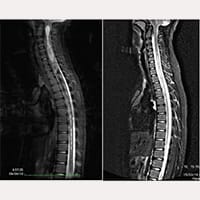

Melanie의 자기 공명 영상

SFT 수술 전

SFT 수술 후

Melanie 상태는 나빠지기 시작했습니다. 끊임없이 울었고 고통에 몸부림쳤습니다. 2008년 새 MRI 촬영을 했고 영상에서 C4와 T7사이의 척수 공동을 볼 수 있었습니다.

일주일 후 퇴원해서 저희는 Gubbio로 돌아왔습니다. 하지만 제 딸의 상태는 계속 좋지 않았고 앉아있을 때도 균형을 잃었습니다. 다른 MRI 촬영 후, 척수 공동이 C1에서 T11까지 커져 있다는 것을 발견했습니다.